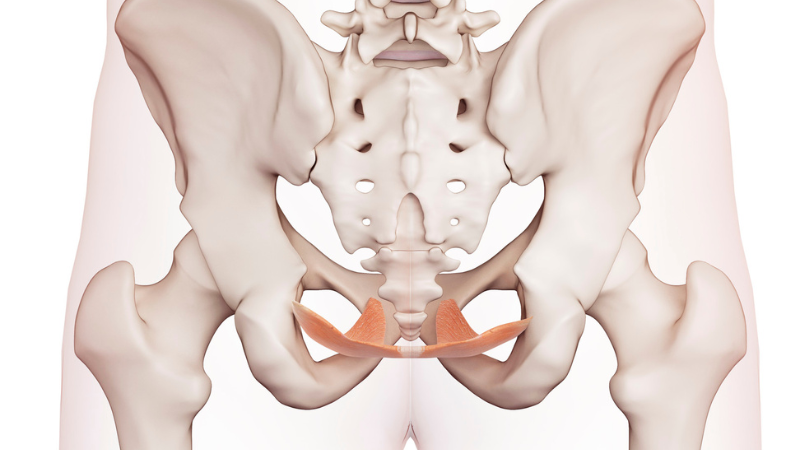

骨盤底筋とはどんな筋肉?

骨盤底筋は、骨盤の底にハンモックのような形で張り巡らされた筋肉群です。

主に、以下の3つの重要な役割を担っています。

内臓を下から支える

骨盤内には、女性であれば子宮、男女ともに膀胱や直腸といった臓器が収まっています。骨盤底筋は、これらの臓器が下に落ちないよう、重力に逆らって適切な位置でしっかりと支える役割を担っています。

排泄をコントロールする

骨盤底筋は、尿道や肛門の周囲を取り囲んでおり、筋肉を『締める・ゆるめる』ことで、排尿や排便、さらにはおならまでもをコントロールしています。トイレの我慢や排泄のタイミングを調整する「要」となる筋肉なのです。

体幹を安定させる

骨盤底筋は、お腹の深層部の筋肉、コアマッスル(横隔膜、腹横筋、多裂筋)の1つであり、「インナーユニット」として体幹の安定に深く関わっています。

ここがゆるむと、体幹の軸が不安定になり、姿勢や体型の崩れにもつながります。